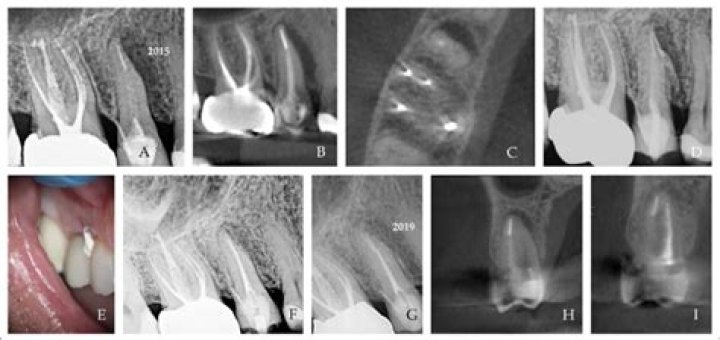

Introduction. Asymptomatic apical periodontitis (AAP) is defined as a chronic inflammation and destruction of apical periodontium caused in response to bacterial infection of the root canal system, which appears as an apical radiolucent area, and does not produce clinical symptoms (1).

Periapical radiolucency is the radiographic sign of inflammatory bone lesions around the apex of the tooth.

To show that teeth with large radiolucencies can be treated/retreated endodontically. To demonstrate that large amount of bone can be regenerated without any bone grafts. That it takes a committed patient and clinician to see cases such as this through to successful treatment.